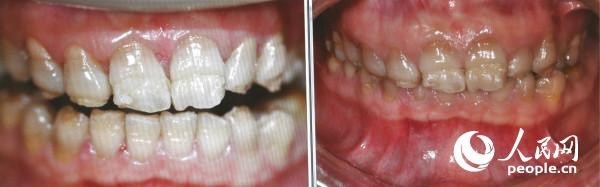

四環(huán)素牙治療前后對(duì)比圖 (人民網(wǎng)記者張希 攝)

人民網(wǎng)北京9月20日電 今天為“全國(guó)愛牙日”,記者就牙齒健康問題采訪了蓋德口腔國(guó)際醫(yī)療中心醫(yī)療總監(jiān)、牙周與美學(xué)修復(fù)專家李秀紅。李醫(yī)生提到,四環(huán)素牙是因?yàn)樗沫h(huán)素進(jìn)入人體之后,分布于各個(gè)器官和組織,被牙齒吸收之后與鈣作用,形成四環(huán)素與鈣的復(fù)合物。牙釉質(zhì)發(fā)育需要鈣質(zhì),而四環(huán)素與鈣結(jié)合會(huì)導(dǎo)致鈣質(zhì)的缺失,這會(huì)導(dǎo)致牙釉質(zhì)發(fā)育不全,俗稱“四環(huán)素牙”。李醫(yī)生介紹,四環(huán)素牙是六七十年代較為常見的疾病,隨著四環(huán)素的使用減少,八、九十年代后四環(huán)素牙少見。四環(huán)素牙由于釉質(zhì)發(fā)育不全,容易磨損,出現(xiàn)深的黃或青、灰的牙本質(zhì)顏色,影響美觀。

如何治療四環(huán)素牙呢?李秀紅介紹說:“在以前,改善四環(huán)素牙顏色的常見方法是做烤瓷牙。即把病人的牙齒磨小并為其戴上烤瓷牙套,這種方法對(duì)牙齒有一定傷害,甚至?xí)䲟p傷牙神經(jīng)。現(xiàn)在四環(huán)素牙可以通過美白的方法改善顏色問題,對(duì)牙齒沒有傷害,牙齒也不會(huì)出現(xiàn)敏感,疼痛。”(實(shí)習(xí)生李星星)